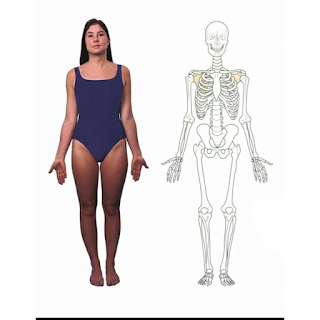

Gambar : mid sagital plane ( membagi tubuh menjadi bagian kiri dan bagian kan )

Mid coronal plane (membagi tubuh menjadi bagian anterior dan posterior)